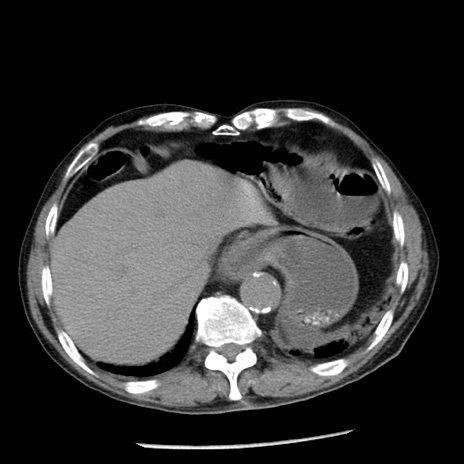

症例26(横断像)

【症例】80歳代男性

【主訴】嘔吐

【現病歴】昨晩2回嘔吐あり、今朝になっても嘔吐あり。来院。

【既往歴】胃潰瘍

【身体所見】意識清明、BT 37.6℃、BP 166/95mmHg、HR 100bpm、SpO2 97%、腹部:平坦・軟、腸蠕動音聴取良好、圧痛なし。

【データ】WBC 21900、CRP 1.46